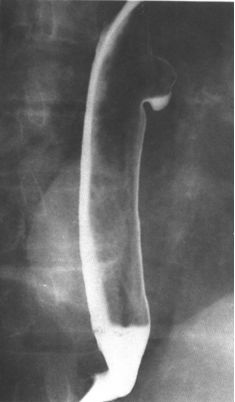

贲门失弛缓:鸟嘴征。

中度贲门失迟缓

重度贲门失迟缓